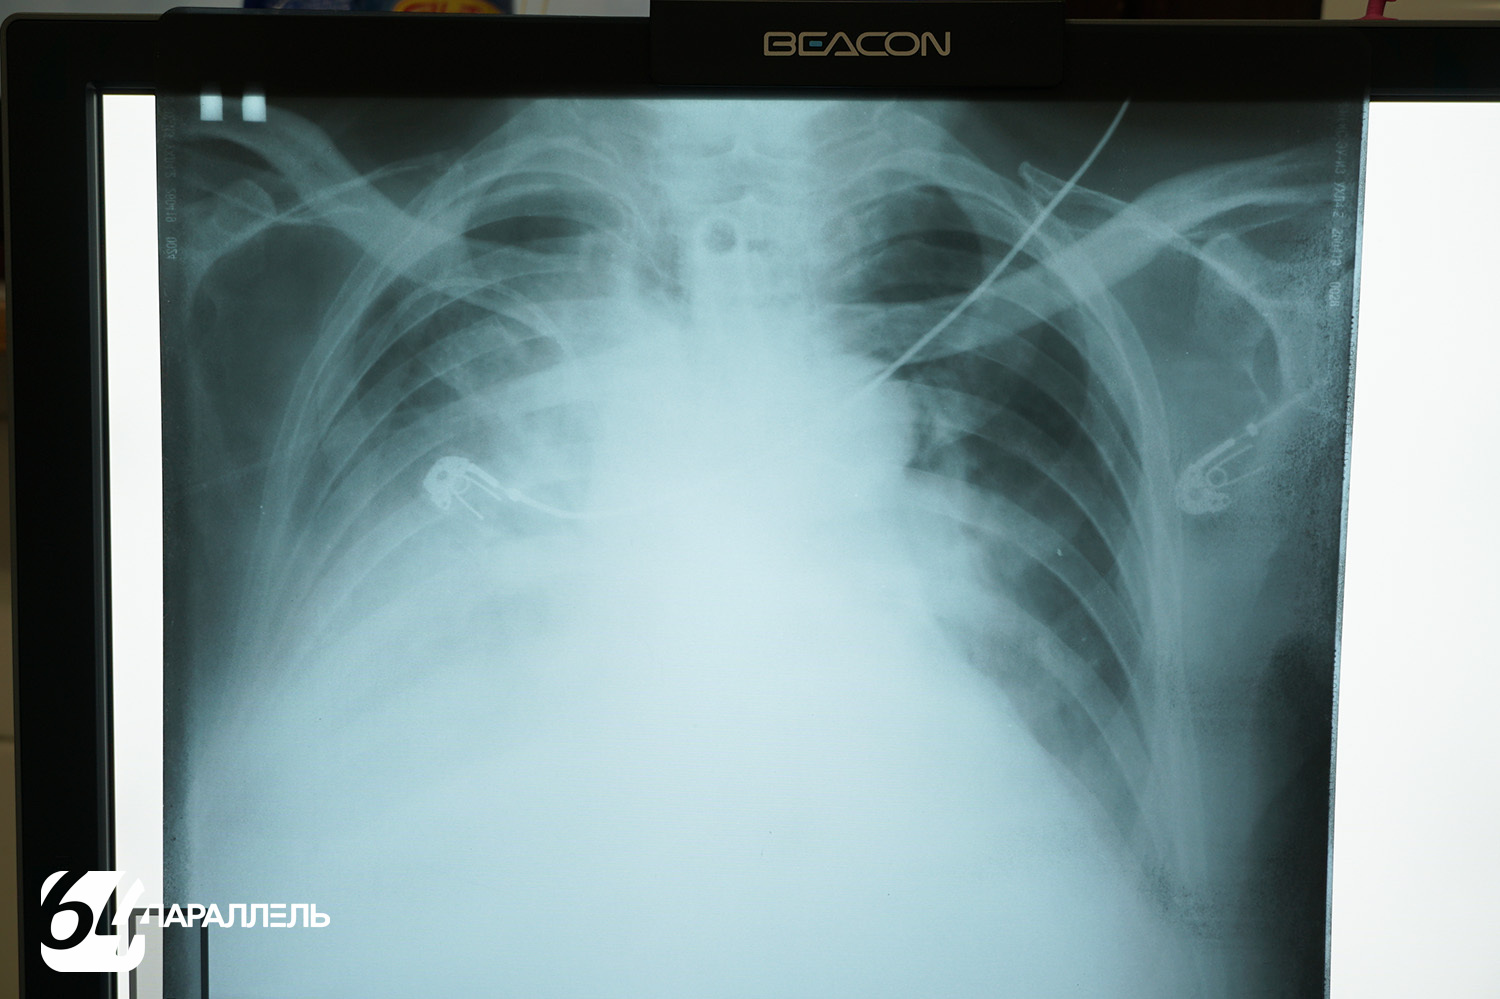

У нового аппарата множество преимуществ. Так, теперь получают качественные цифровые снимки с обширной постпроцессинговой обработкой: их можно увеличивать, уменьшать, менять яркость и контрастность, детально рассматривать зону интереса, что невозможно было сделать на аналоговых снимках. Также аппарат позволяет выполнять полипозиционные исследования, при этом не нужно менять положение пациента. Таким образом можно из разных точек заглянуть «внутрь» человека, не двигая его. Это особенно важно для маломобильных и тяжёлых пациентов. На трубке аппарата установлена видеокамера, которая передает изображение на консоль оператора, и пациент всё время находится на виду.

– Новый аппарат просто космос! Получаемые снимки выводятся сразу на монитор. Качество изображения потрясающее. Теперь мы меньше будем работать в фотохимической лаборатории в темноте, что сохранит нам здоровье и зрение, – говорит Екатерина Серикова.